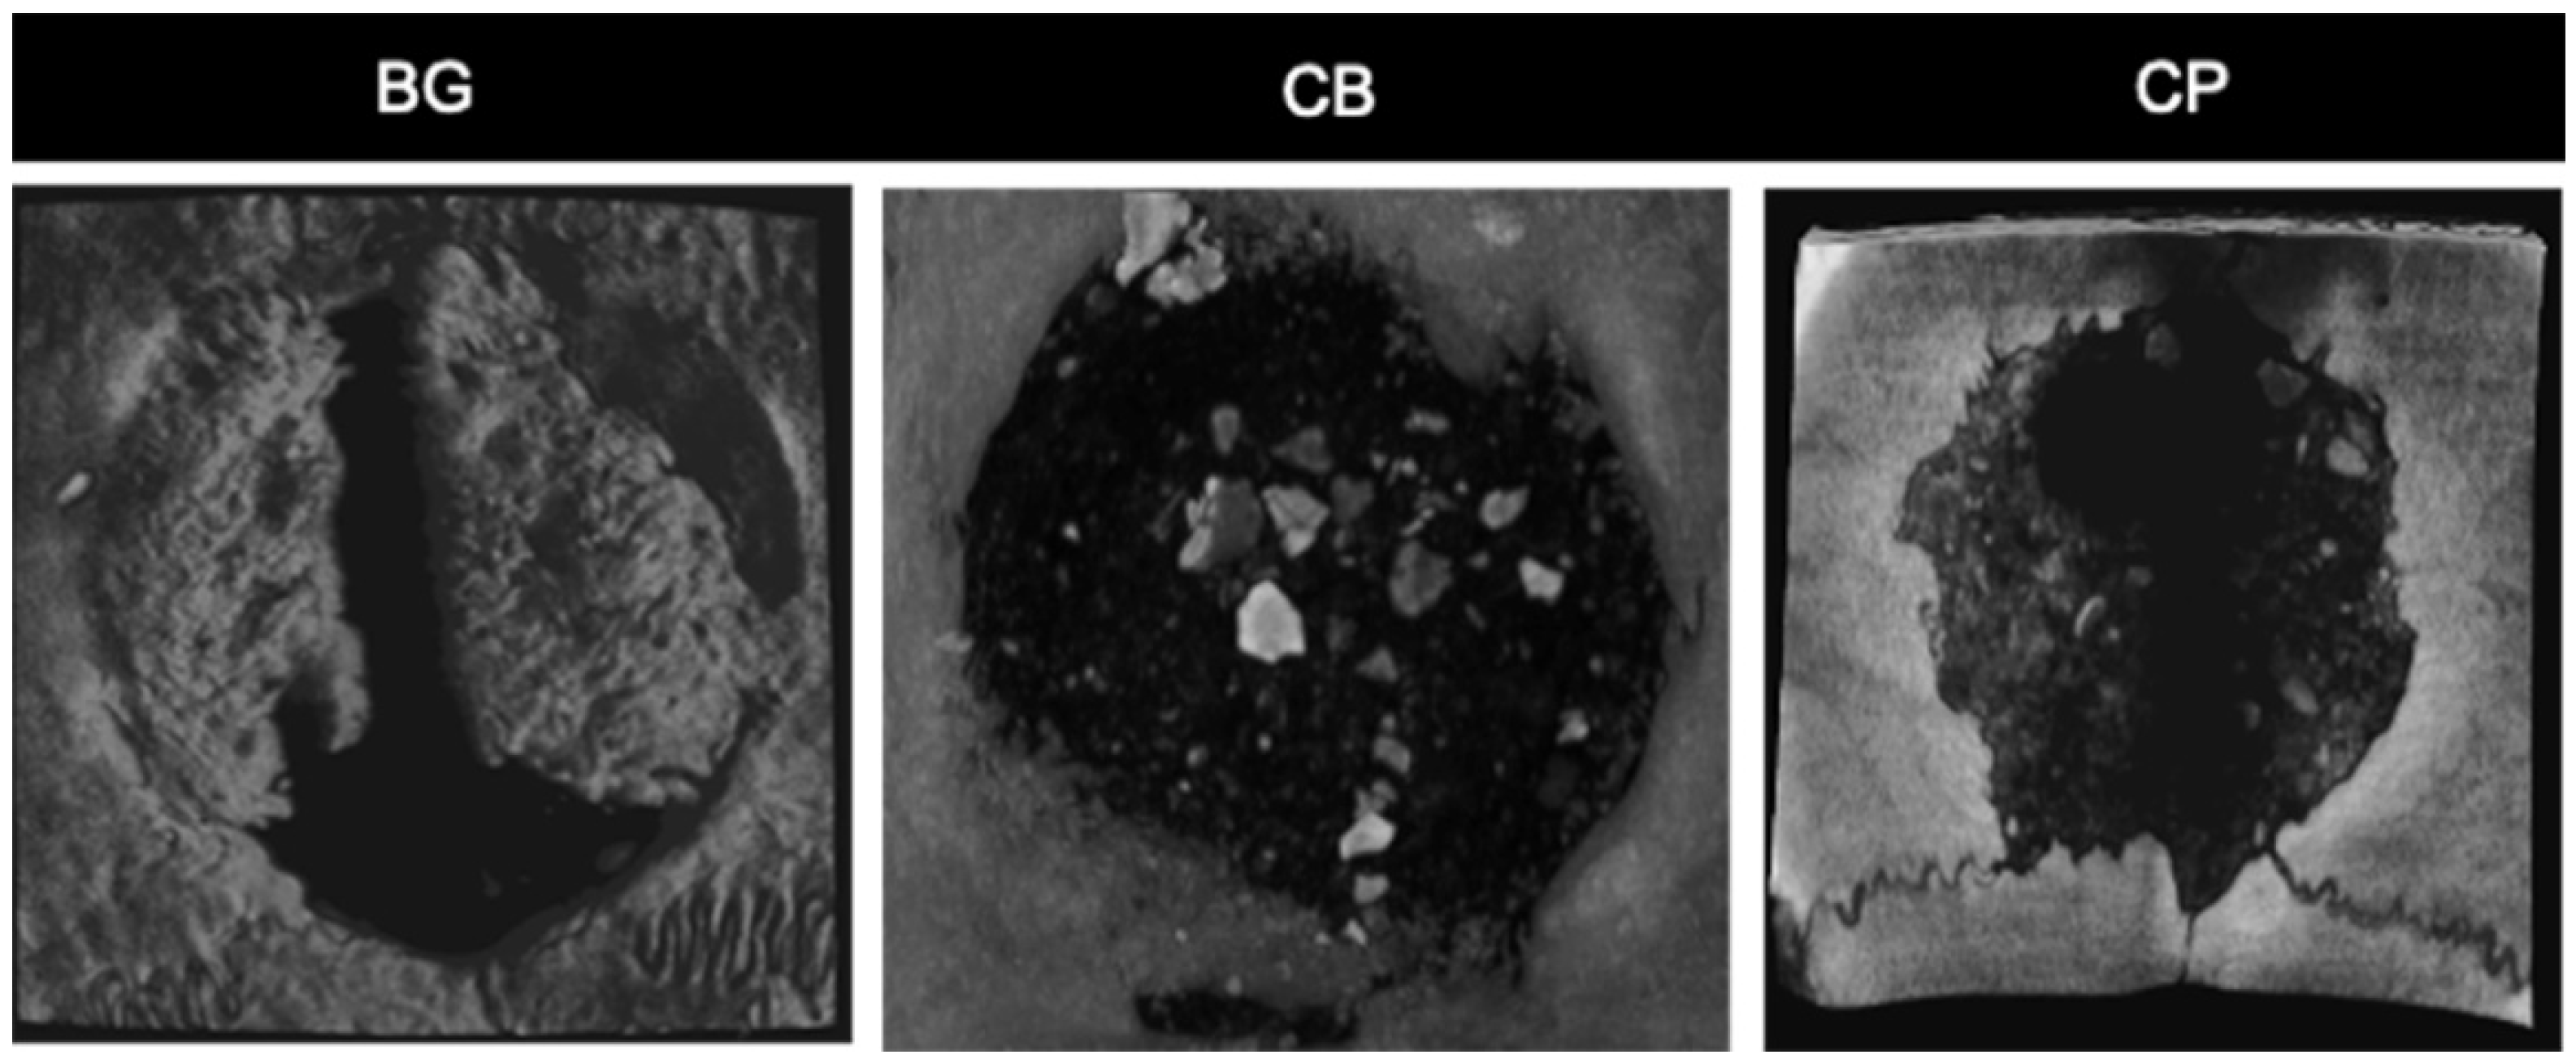

3.1. Histological Analysis

3.5. Microtomography Analysis